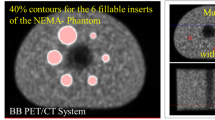

Assessing PET image quality (IQ) remains a challenge due to its clinical subjectivity and difficulties in standardisation. Over the years, there have been described at least four different methods to evaluate the PET image quality: image noise, noise equivalent count rate (NECR), NEMA NU-2 image quality phantom measurements and visual IQ.

The first two are automatic and objective measurements determined from the reconstructed image or PET raw emission data of phantoms.

In a first step, all data were automatically analysed using Matlab (MathWorks, Natick, MA, USA) to estimate the NECR versus activity concentration in a similar manner to the National Electrical Manufacturers Association (NEMA) analysis and based on previous publications [8]-[12]. This measurement is essentially the same usually performed on phantom data, but the required data (the number of true, scattered and random counts) are estimations either provided by the scanner software or automatically extracted from the reconstructed image. To determine the NECR for a bed position of patient data, the following steps were used: the PET raw data files were used to measure prompts and to calculate randoms from singles and obtain the bed position duration. Then, the reconstructed PET images were used to obtain an estimate of the model-based scatter fraction. With those two items, the NECR was calculated for each bed position, and the patient NECR was an average of all whole-body bed positions. By using the PET images, voxels above a fixed activity concentration of 1.0 kBq/mL, the average activity concentration for all voxels in the bed position was calculated. Decay to each bed position based upon its start time relative to scan start was applied as well.

Concerning NECR, there was a statistically significant difference between the four BMI groups (p < 0.01), except between groups II and III. Concerning IQL, there was a statistically significant difference between the four BMI groups (p < 0.01), except between groups III and IV (see Table 3). A graphic showing the relations of IQL average and NECR average per BMI groups and the correlation of IQL and NECR for all BMI groups are represented in Figure 7.